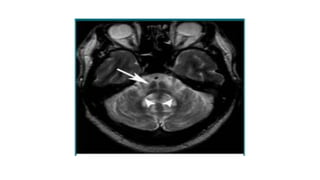

 MRI-

midbrain atrophy(appearance of a flat or concave profile -68% sensitivity and an 89%

specificity

Superior cerebellar peduncle atrophy.

“morning glory flower sign” and the “hummingbird sign” – Highly specific(100%) low

sensitivity (50% and 68.4%)

magnetic resonance parkinsonism index (MRPI) - sensitivity of 100%

and specificity of 99·2–100·0% for PSP-RS.

pons:midbrain ratio-